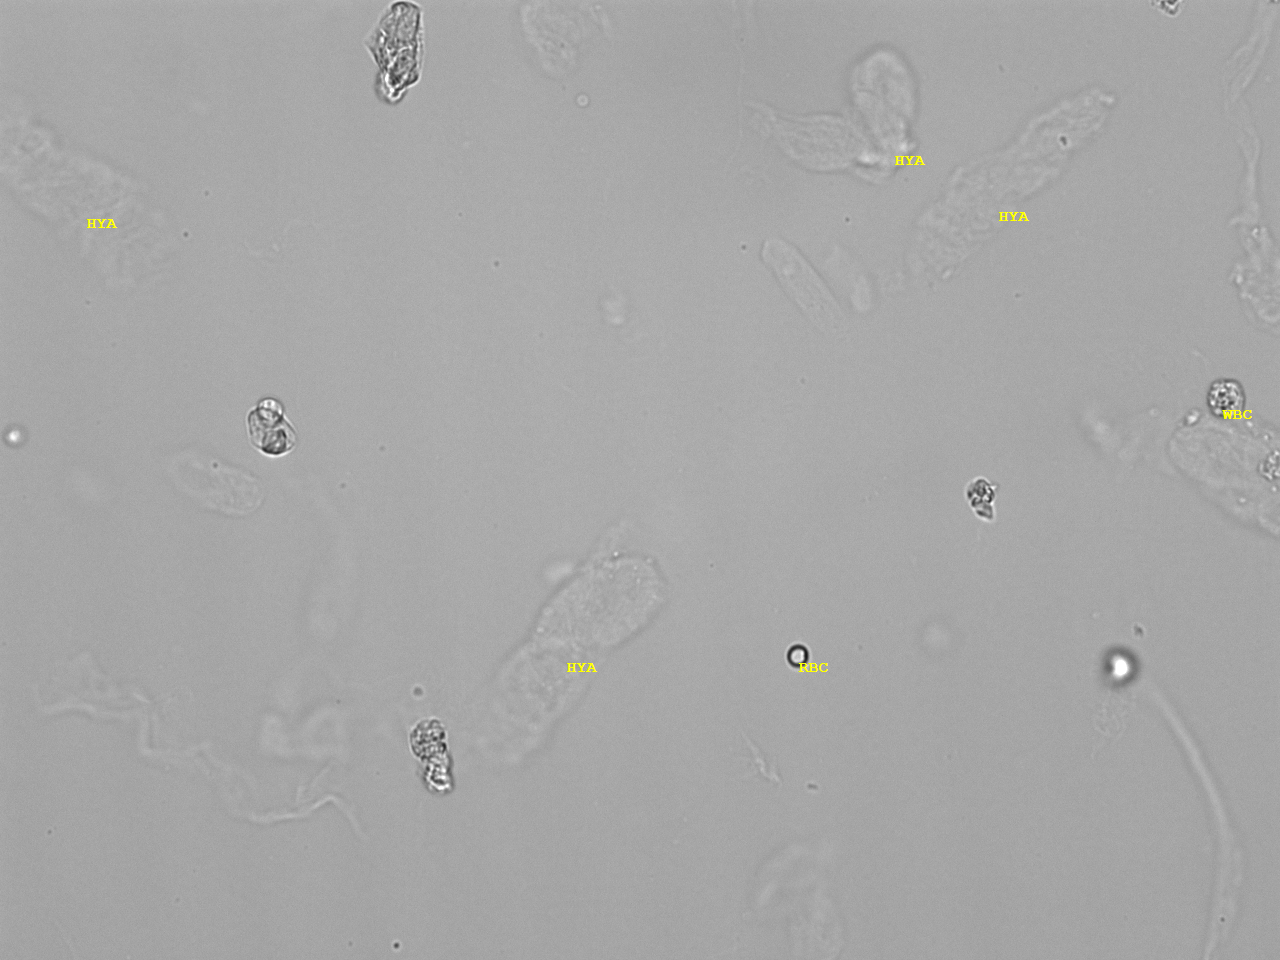

Urin-Feature: hyaline Zylinder